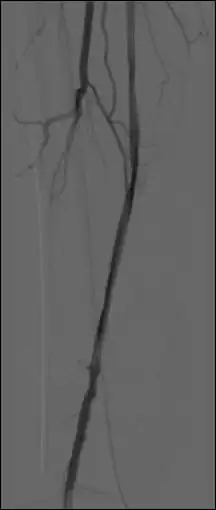

The image number used for the mask image is displayed – the first image of the sequence is the default mask. Browse through the sequence and adjust the WL/WW as needed. Click on the ‘current’ button to select another mask image.

Use the up/down arrows to shift the relative position of the mask and live images in single pixel increments in both horizontal (X) and vertical (Y) dimensions, if needed.